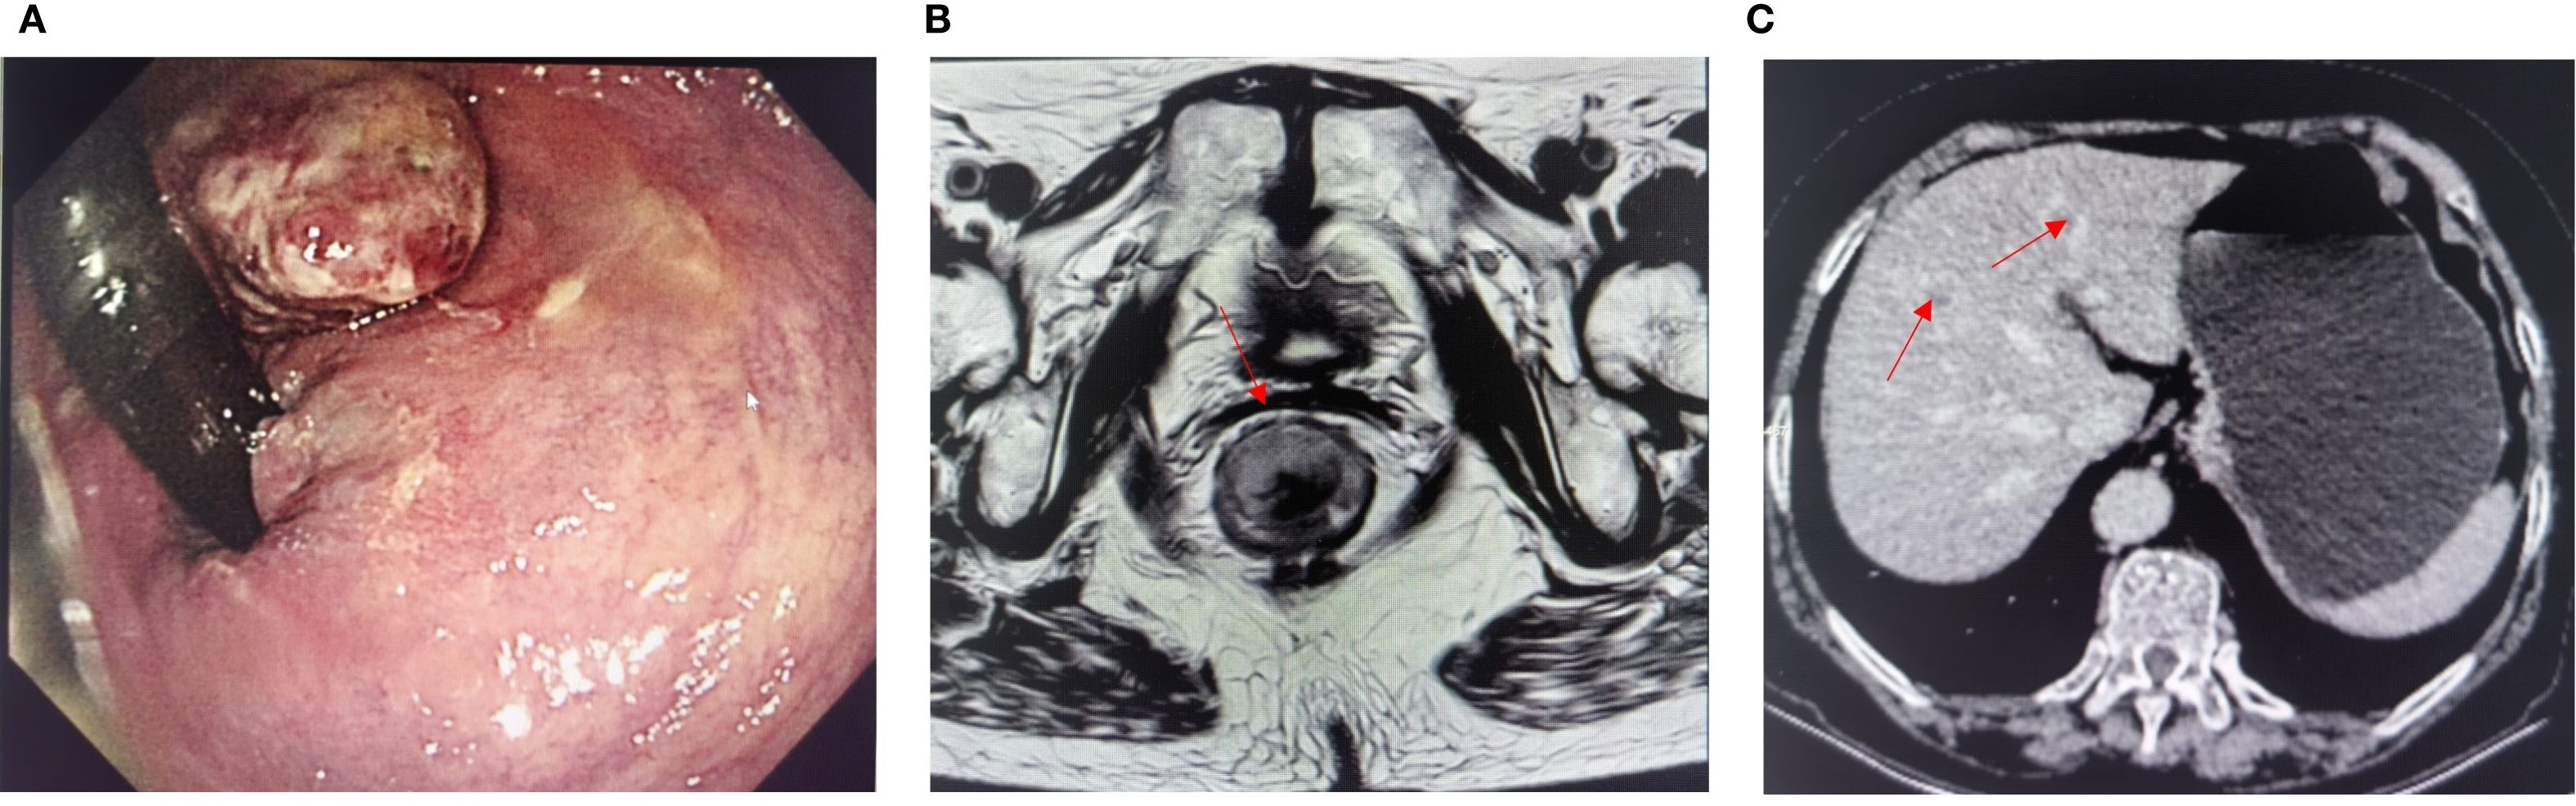

A 66-year-old woman with a complaint of intermittent anorectal bleeding and pain for 1 month. During this period, she underwent a colonoscopy at a local hospital, which revealed the presence of a rectal tumor. Due to limited medical conditions in local hospitals, surgical treatment was not performed. Subsequently, she presented to our hospital. The patient has no history of harmful habits or significant past medical conditions, and there is no relevant family history of genetic disorders. Physical examination revealed a non-tender mass measuring 4 × 3 centimeters in the anorectal region, located approximately 4 cm from the anal margin. Colonoscopy showed a rectal lesion of about 4 cm × 3 cm × 3 cm, located within 5cm of the anal verge, with visual erosion and hemorrhage (Figure 1A). Biopsy was taken for the final diagnosis. Rectal magnetic resonance imaging (MRI) showed a soft tissue mass protruding from the rectal wall, with no local lymph node enlargement (Figure 1B). Enhanced computed tomography (CT) of the chest and abdomen detected an occupying lesion protruding from the rectal wall into the intestinal lumen, as well as a circular low-density shadow in the 4/8 liver segment along with mild enhancement. No lymph node enlargement was found in the local area. (Figure 1C). Hematological examinations, in review including blood count, biochemical tests, carcinoembryonic antigen, and alpha-fetoprotein levels, were within normal ranges, except that CA 199 was 29.70U/ml. Histological biopsy findings (HE staining) showed that the tumor was composed of spindle-shaped and oval-shaped cells, exhibiting significant cellular atypia and nuclear division. Immunohistochemical staining revealed positive results for HMB 45. Expression of S-100 was negative. The expression level of Ki67 was 40%. Based on the histopathological cell morphology, immunohistochemistry, and imaging examination, the patient was preliminarily diagnosed with a primary AMM with liver metastasis. After obtaining written informed consent. The patient underwent transanal local resection for primary AMM and ultrasound-guided radiofrequency ablation for liver metastases. Postoperative contrast-enhanced ultrasound demonstrated complete inactivation of the liver metastases (Figures 2A, B). The postoperative pathological examination results (HE staining) revealed negative margins, and the tumor cells exhibited spindle-shaped, oval-shaped, and pleomorphic types (Figures 3A, B). The immunohistochemical analysis showed positive staining for SOX100, S-100, HMB-45, Mela A, PRAME, p16, and ki-67 (+70%) (Figures 3C-I). Genetic testing identified a mutation in exon 17 of the KIT gene (D820Y), while both the BRAF and NRAS genes were found to be wild-type. The patient recovered well and was discharged on the sixth day after surgery. Three weeks post-surgery, whole-body bone imaging and enhanced CT scans of the chest and abdomen were performed. The results showed that the patient experienced no complications related to the surgery and no signs of tumor recurrence. Blood cell counts and biochemical tests were normal, with the CA 19–9 level at 31.30 U/ml. Subsequently, targeted therapy with imatinib was initiated at a dosage of 400 mg per day. CT scans of the chest, abdomen, and pelvis were performed every two months. However, after 14 weeks of imatinib treatment, the patient experienced intermittent abdominal pain. The blood routine test was normal. Biochemical tests revealed elevated levels of bilirubin, ALT, and AST, with the AST level exceeding 3-fold the upper limit of the normal reference value. The D-dimer level was measured at 4.04 µg/mL. Tumor markers: CA199 was 210.00U/ml, CA125 was 72.80U/ml. A CT scan revealed a portal vein thrombosis, along with new metastases in the liver and lungs (Figures 2C, D). No new lesions were found in the anorectal area. An ultrasound of both lower limb blood vessels showed no abnormalities. The patient discontinued imatinib and started receiving anticoagulant and hepatoprotective medication; however, the symptoms did not improve. As a result, the patient forwent further treatment and was discharged, dying two weeks later (Figure 4).

Figure 1. (A) Preoperative colonoscopy image. (B) Magnetic resonance imaging evaluation before surgery. (C) Enhanced CT showed liver metastases (red arrows indicate lesions).